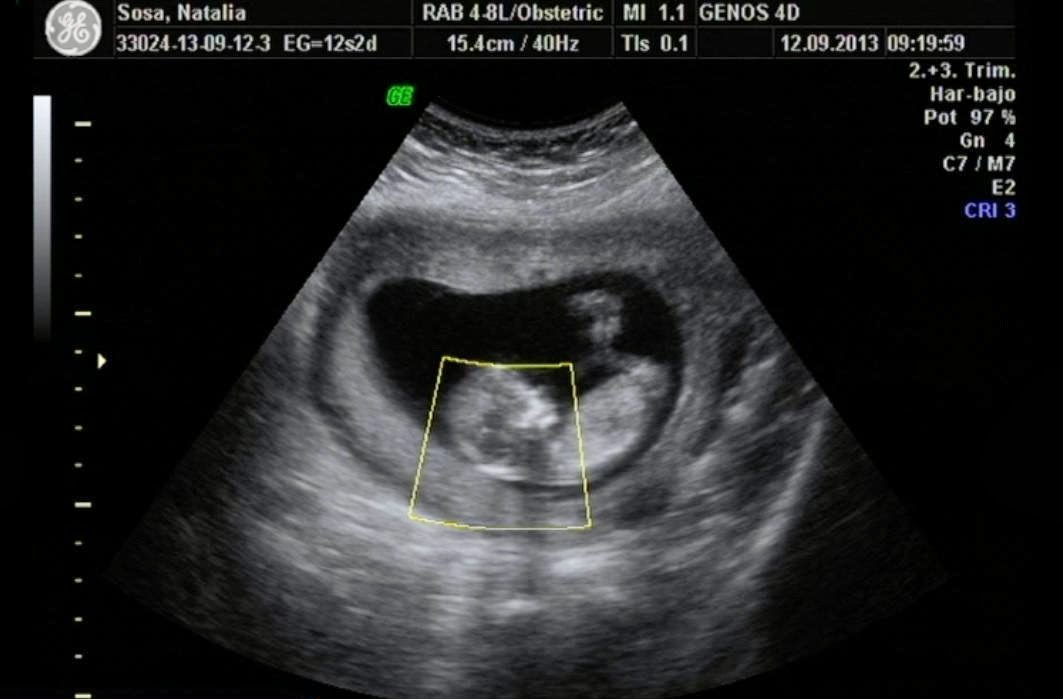

Aunque te hayan podido realizar alguna antes por diversas razones, como ocurre en el seguimiento de los embarazos mediante técnicas de reproducción asistida, en las amenazas de aborto o simplemente porque hayas "pedido el favor", en un embarazo normal la primera ecografía que tiene valor es la que se te debe realizar entre las semanas 11 y 14, cuando tu feto mide entre 4,5 y 8,4 centímetros.. Ecografía de la semana 32-36. La ecografía del tercer trimestre de gestación va encaminada, fundamentalmente, a determinar la estática fetal (posición del feto dentro del útero), la localización de la placenta, la valoración de la cantidad de líquido amniótico (el líquido amniótico es un indicador de bienestar fetal, cuando.